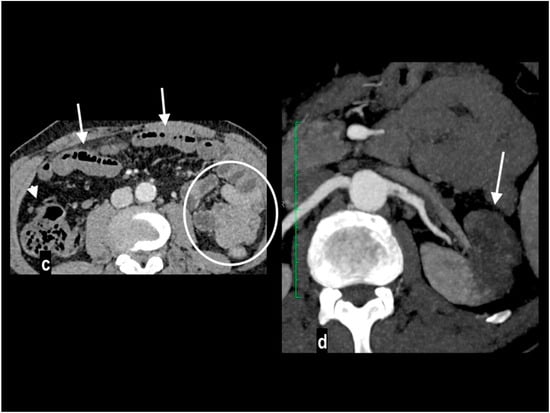

Figure 8.

Acute abdominal pain in a 66-year-old woman. Atheromasic low-density plaque at the proximal SMA with luminal stenosis ((a) arrow). Dilated paper-thin small intestine wall ((b) circle). Segmentary transmural necrosis was observed on the mesenteric side of an intestinal loop (arrow), intestinal wall line loss and periparietal fluid effusion (c). The patient underwent surgical resection of the necrotic loop.